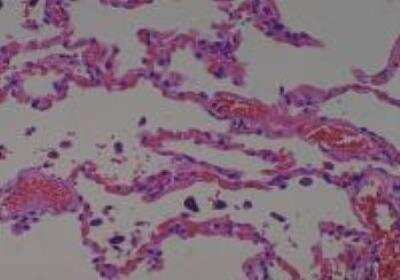

Scientific Data Images for Human Multi Tissue MicroArray (Normal Adjacent)

Hematoxylin & Eosin Stain: Human Common Tissue MicroArray (Normal Adjacent) [NBP2-30215] - 103. Stomach